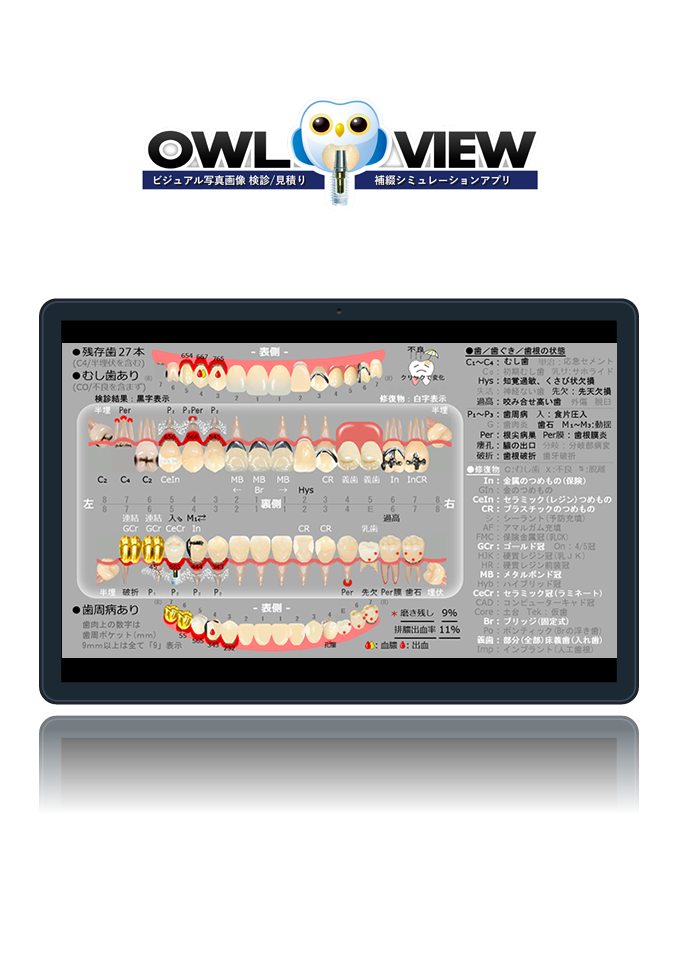

ビジュアルな写真画像での歯管、検診書類を正確、簡単、1シートで!

今まで何枚もの検診情報がたった1枚で。

歯科医師と患者様の為に開発されました

より便利に、より分かりやすく。

検診/歯管

これはサンプルの説明文です。各箇所に短めの説明文を入れます。これはサンプルの説明文です。各箇所に短めの説明文を入れます。